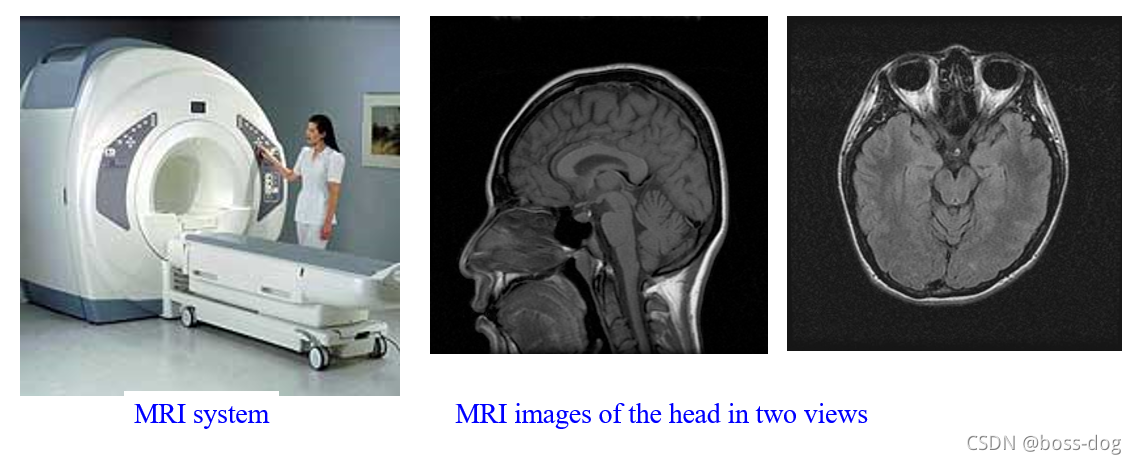

3.磁共振成像(Magnetic Resonance,MR)。采用的是射频电波,安全且没有核辐射;应用领域如解剖成像(Anatomical imaging)、磁共振做血管成像(MR Angiography)、磁共振做功能成像(Functional MRI)。

Magnetic Resonance Imaging (MRI,磁共振成像)

磁共振对软组织看的更清楚些。

磁共振可以把软骨看得很清楚。